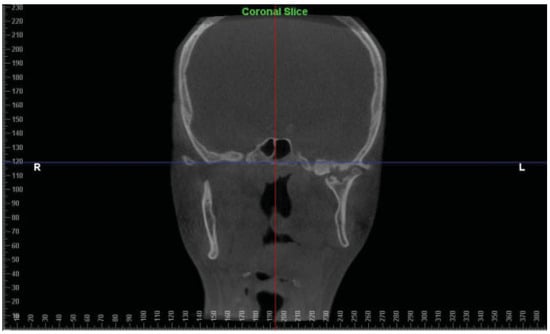

:Case Report